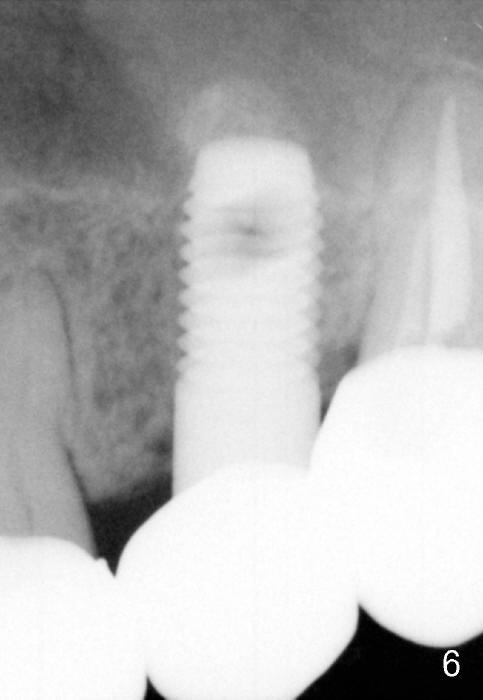

A 59-year-old lady used to have a 3-unit bridge in the upper left quadrant. A 4.5x6mm Bicon implant (Fig.1 B without extruding into the sinus) was placed in the atrophic pontic area 5 months earlier. When the abutment (A) was removed, the implant came out. The osteotomy was processed with a 4.5x14 mm tapered tap, which was unstable. When a 4.8 mm cylindrical tap was placed (past the sinus floor), it was tight (Fig.2). A 5x14 mm cylindrical implant (Fig.3 I) was inserted with elevation of the apparent sinus floor (>, no allograft used in case of sinus infection). Seven months postop, the density of sinus floor increases (Fig.4 <). The implant is stable and processed for crown (Fig.5 C, different view of the lifted sinus floor (<)). While sinus floor density is decreasing, the mesial and distal bone density is increasing 6 months (Fig.6), 1 year 6 months (Fig.7) and 3 year 6 months (Fig.8) post cementation.